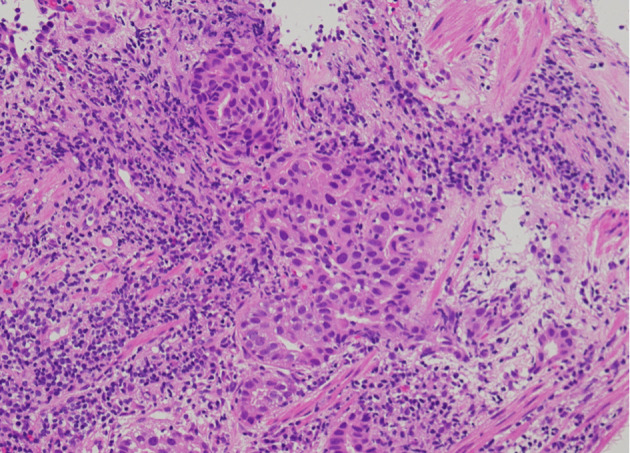

在非小细胞肺癌中发现并开发了各种驱动突变和相应的分子靶向药物。手术标本中发现双原发癌的病例很多。然而,据我们所知,我们的病例是首次报告同步双原发性肺腺癌,且表皮生长因子受体(EGFR)L858R和间质-上皮转化(MET)第14外显子跳越突变。一名 75 岁的日本妇女因胸部 X 光片显示右上肺野有一个不断增大的结节而被转诊至我科,她患有慢性心衰和肾衰竭。胸部计算机断层扫描(CT)发现右侧 S1 肺部有一个结节,左侧 S1+2 肺部也有一个结节。支气管镜活检诊断右侧 S1 结节为中度分化腺癌。右侧 S1 腺癌的 Oncomine Dx Target Test Multi-CDx 系统检测到表皮生长因子受体 L858R 突变。18F-氟脱氧葡萄糖正电子发射断层扫描/CT显示右侧S1和左侧S1+2结节以及双侧气管旁下淋巴结均有异常摄取。我们诊断她的右侧 S1 结节为 c 期 IIIA(cT1bN2M0)腺癌,并怀疑左侧 S1+2 结节为另一种原发性肺癌。考虑到她的一般情况、合并症和意愿,我们开始使用奥希替尼。右侧 S1 癌症取得了部分反应(PR),而左侧 S1+2 结节和淋巴结肿大。左锁骨上淋巴结的抽吸细胞学检查显示为腺癌。FoundationOne® Liquid CDx肿瘤图谱检测不仅发现了表皮生长因子受体(EGFR)L858R,还发现了MET第14外显子跳跃突变。我们诊断左侧S1+2结节为另一种原发性腺癌(cT1bN3M0,c期IIIB),且伴有MET突变,并将奥希替尼改为卡马替尼。虽然左侧 S1+2 癌症通过卡马替尼达到并维持了 PR,但右侧 S1 癌症却有所增加,并出现了几个新的转移灶。随后将卡马替尼换成了奥希替尼,但仍无法控制癌症。在这种情况下,我们尝试根据每种癌症的进展情况,将携带不同两种驱动突变的双原发性腺癌的单一疗法从奥希替尼切换到卡马替尼。时间和空间异质性加强了在怀疑双原发时进行原发组织活检的必要性。可以考虑进行目前尚不规范的不同时间的液体活检。

Various driver mutations and the corresponding molecular-targeted drugs have been detected and developed in non-small cell lung cancer. There were many cases in which surgical specimens had happened to find double primary cancers. However, to our knowledge, our case was the first report of synchronous double primary lung adenocarcinomas harboring epidermal growth factor receptor (EGFR) L858R and mesenchymal-to-epithelial transition (MET) exon 14 skipping mutations. A 75-year-old Japanese woman with chronic heart and renal failures was referred to our department because of a growing nodule in the right upper lung field on chest X-ray films. Chest computed tomography (CT) detected a nodule in the right S1 and another nodule in the left S1+2. Bronchoscopic biopsy diagnosed the right S1 nodule as moderately differentiated adenocarcinoma. Oncomine Dx Target Test Multi-CDx system of the right S1 adenocarcinoma detected EGFR L858R mutation. The 18F-fluorodeoxyglucose positron emission tomography/CT showed abnormal uptakes both in the right S1 and the left S1+2 nodules, and in the bilateral inferior paratracheal lymph nodes. We made a diagnosis of c-stage IIIA (cT1bN2M0) of adenocarcinoma in the right S1 and suspected another primary lung cancer in the left S1+2. Considering her general conditions, comorbidities and wishes, we started osimertinib. The right S1 cancer achieved partial response (PR), while the left S1+2 nodule and lymph nodes enlarged. Aspiration cytology from the left supraclavicular lymph node showed adenocarcinoma. The FoundationOne® Liquid CDx tumor profiling test detected not only EGFR L858R, but also MET exon 14 skipping mutation. We made a diagnosis of another primary adenocarcinoma from the left S1+2 nodule (cT1bN3M0, c-stage IIIB) with MET mutation, and changed osimertinib to capmatinib. Although the left S1+2 cancer achieved and maintained PR by capmatinib, the right S1 cancer increased, and several new metastases appeared. The subsequent switch from capmatinib to osimertinib could not control cancers. In this case, we tried to switch monotherapies from osimertinib to capmatinib for double primary adenocarcinomas harboring different two driver mutations, according to each cancer progression. The temporal and spatial heterogeneity reinforces the need for primary tissue biopsy if dual primaries are suspected. Temporally distinct liquid biopsies, not standard at present, may be considered.